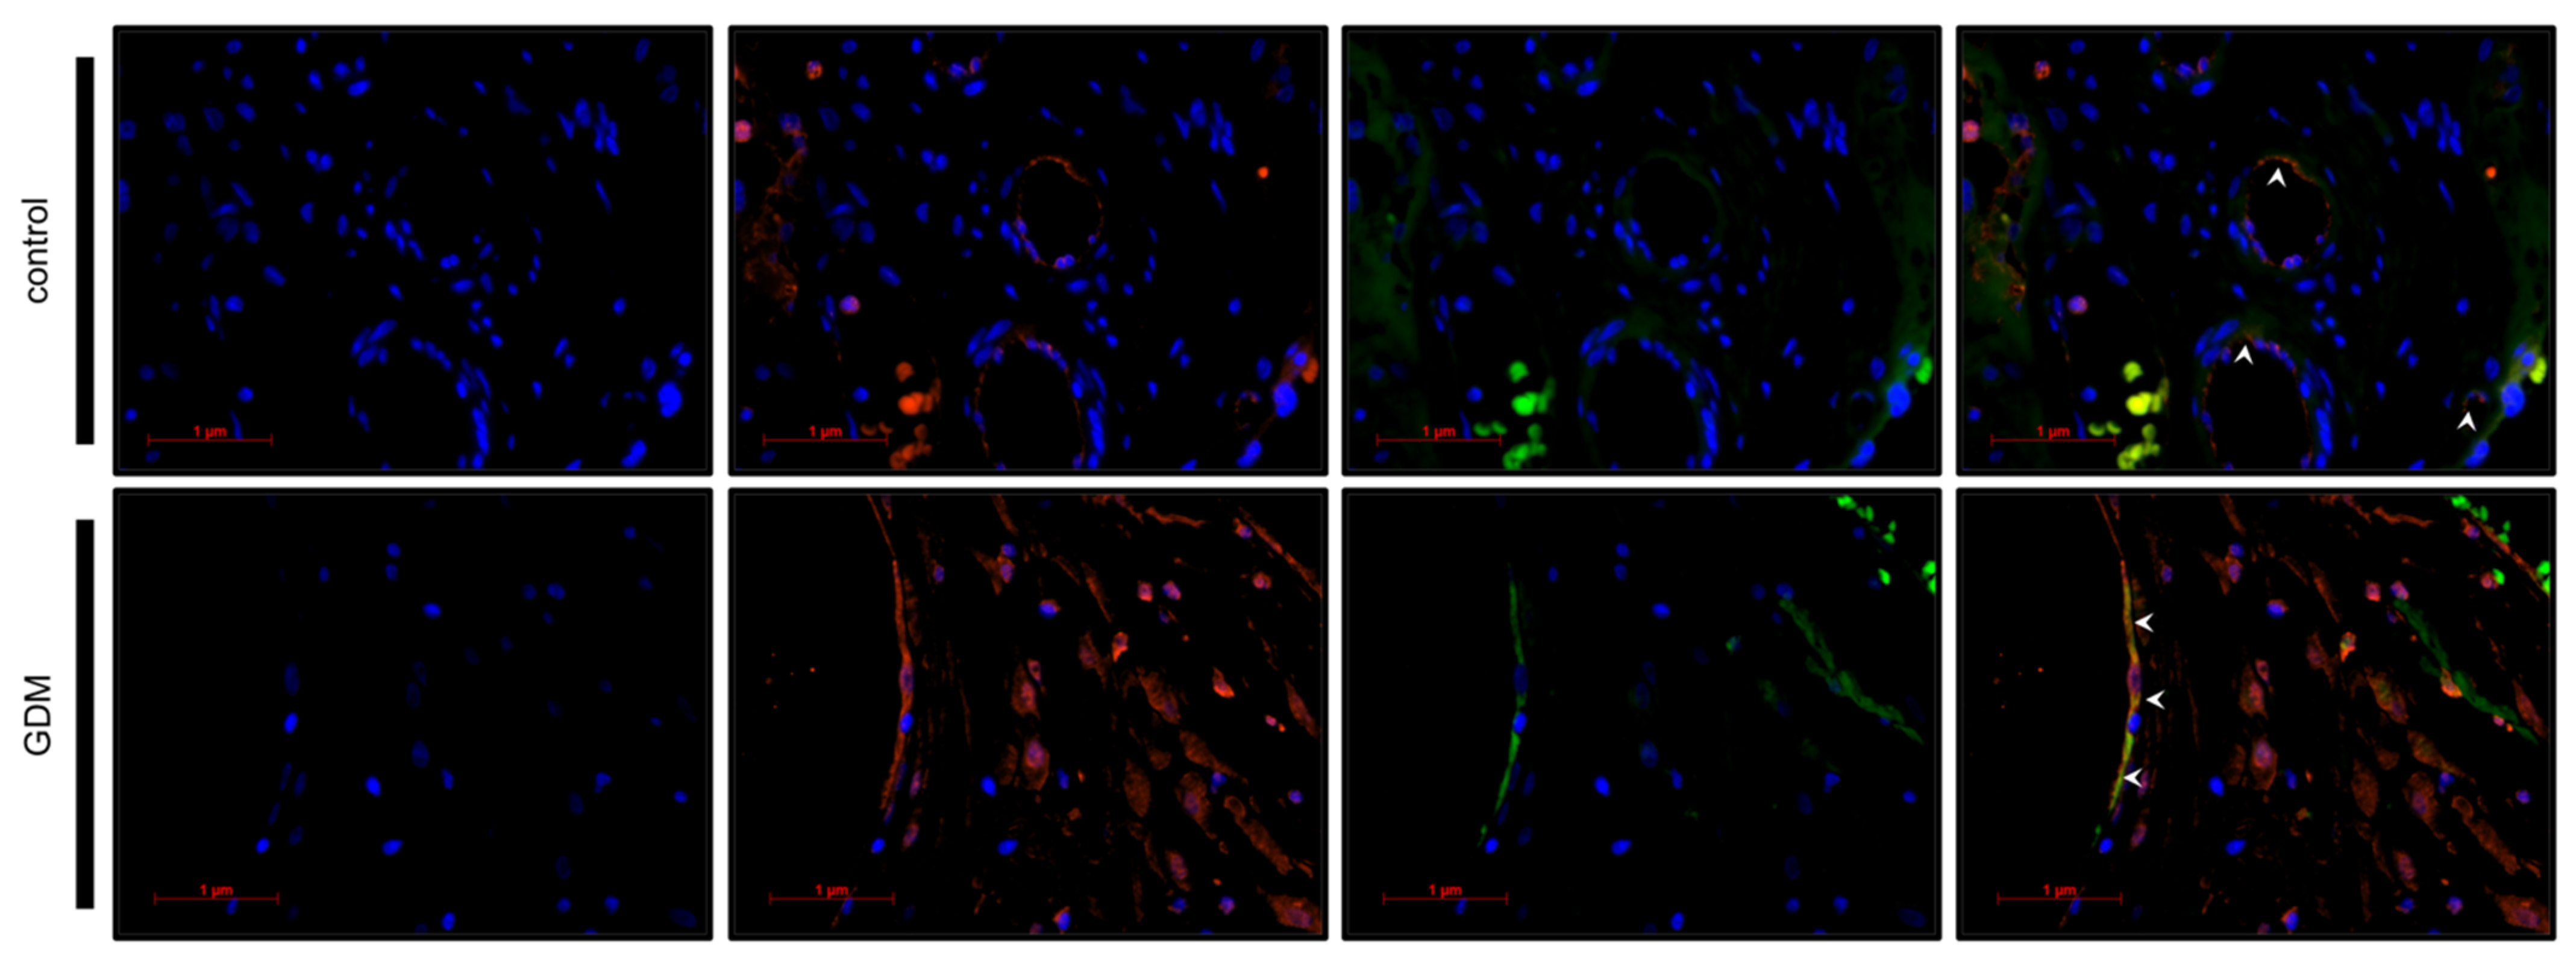

2.5. Identification of Galectin-2 Expressing Cells by Immunofluorescence Double Staining